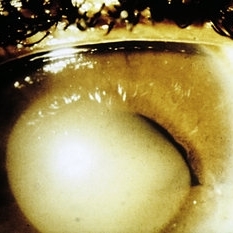

Slide 7-41

Feb 25 2019 by Lancaster Course in Ophthalmology

Keratoconus showing central thinning and scarring of the corneal button.

Condition/keywords: cornea, scar